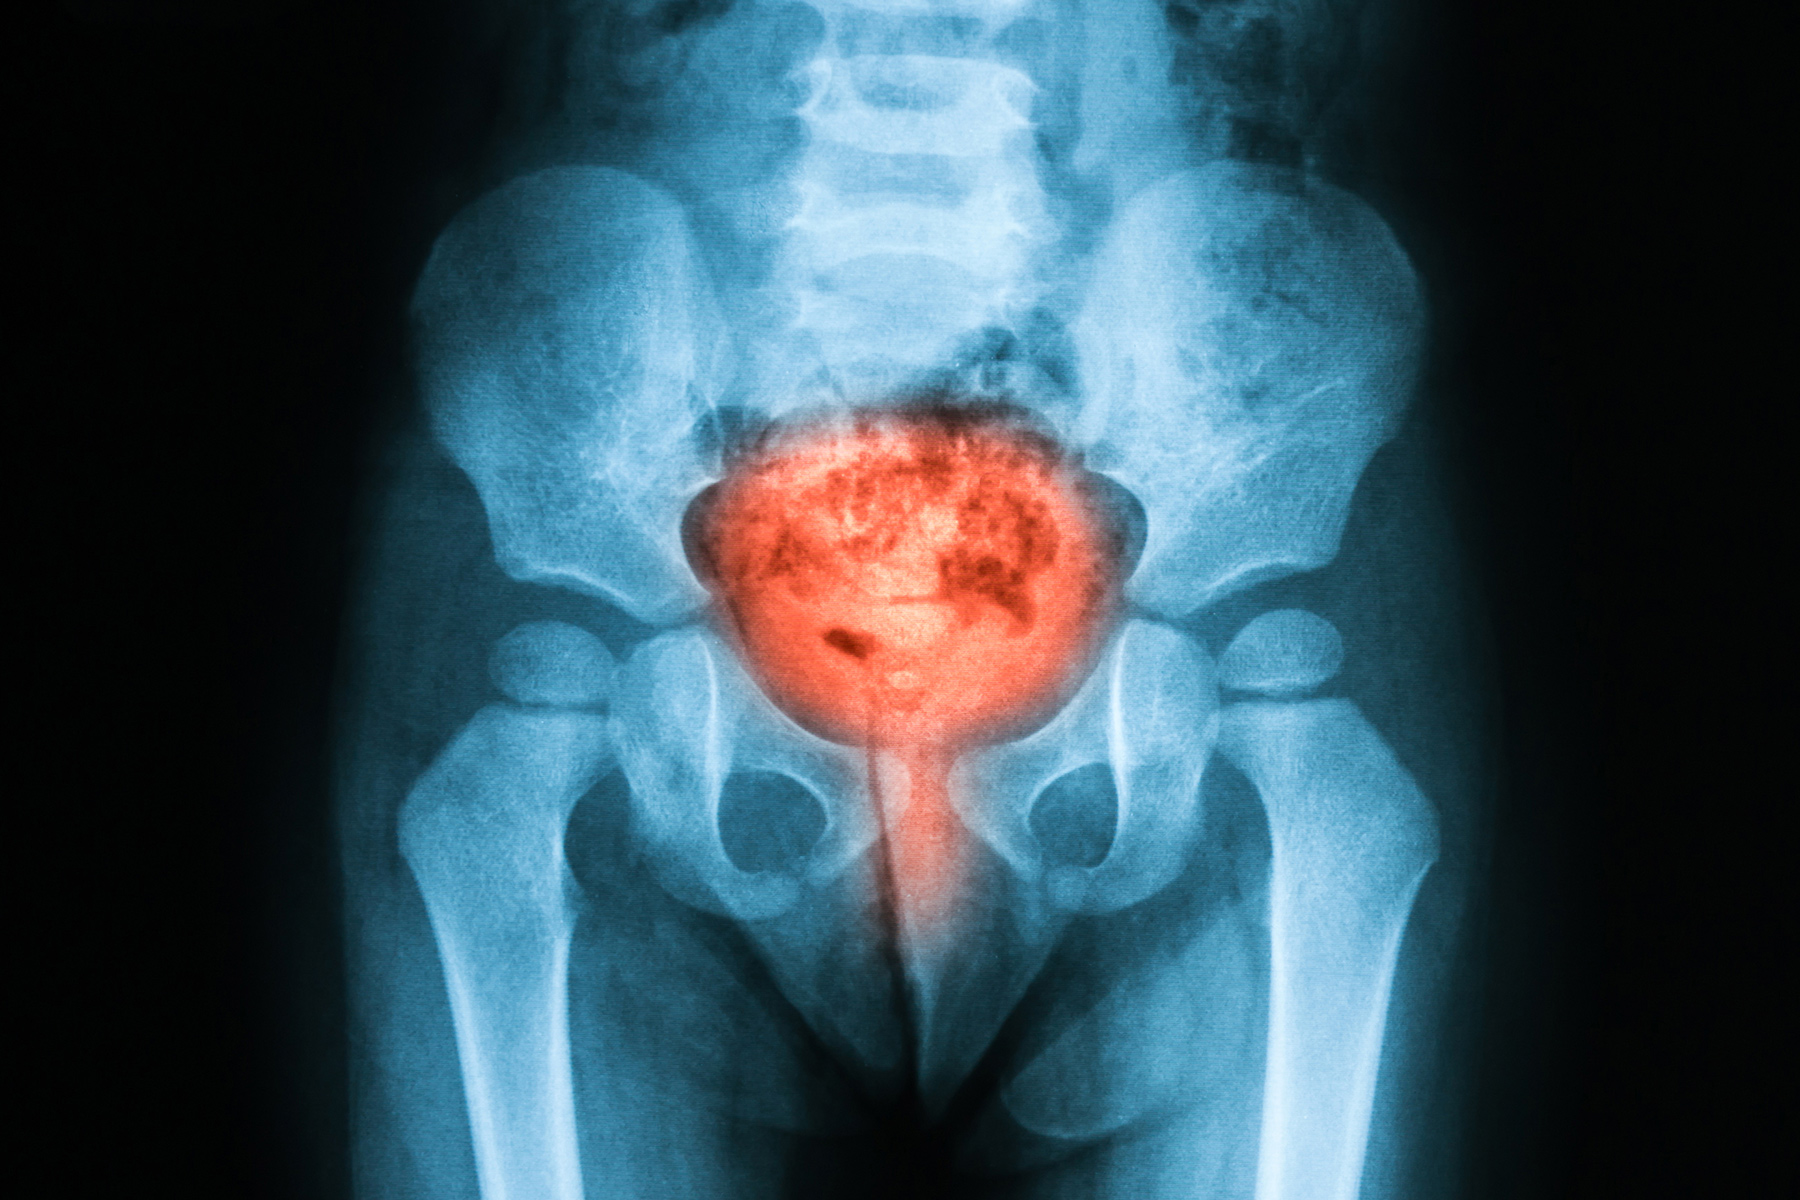

膀胱疼痛综合症

老想去洗手间,但每次尿得很少。下腹部也可能会疼痛,当您尿尿时,疼痛会加剧,当膀胱组织发炎时就会出现这种情况,且非常敏感时。尚不清楚原因。可以通过饮食和运动,药物治疗,手术和物理疗法来治疗这种情况,也称为间质性膀胱炎。